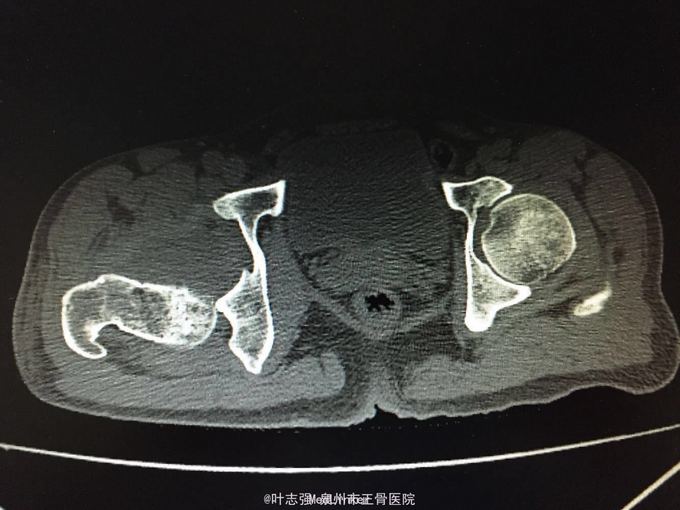

髋臼骨折伴髋关节后脱位ORIF

车祸致左髋部疼痛、活动受限1天。 53岁男性

左髋臼骨折伴髋关节后脱位 行生命支持,股骨髁上骨牵引,